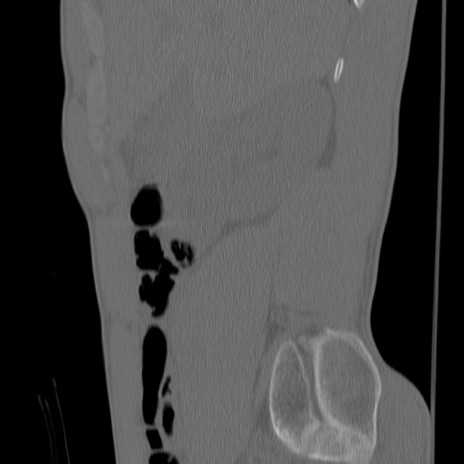

症例3 腰椎CT(矢状断像)

【症例】30歳代男性

【主訴】腰痛

【現病歴】本日旅行先で観光中に、友人と衝突し転倒し受傷。

【身体所見】麻痺なし、右下腿内側前面外側、左下腿内側に知覚鈍麻・しびれ

異常所見と診断は?

腰椎CT